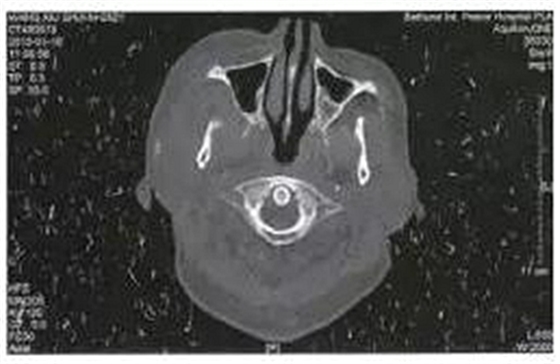

病例3,男,52歲。2月前發(fā)現(xiàn)右側(cè)上頜后牙疼痛,局部腫脹,應(yīng)用廣譜抗生素后有所減輕,但不能完全恢復(fù)。入院10天前右側(cè)面部、顳部腫痛加重,并張口受限明顯?;颊哂刑悄虿∈非抑委煵灰?guī)范。檢查右側(cè)顳部腫脹明顯,張口度10 mm,右側(cè)上頜第三磨牙深齲。CT示右側(cè)翼頜間隙及顳間隙腫脹,右側(cè)緣突骨質(zhì)破壞,在其前方形成液化區(qū)(圖3)。以間隙感染收入院后全麻下手術(shù),口外顳部和口內(nèi)右側(cè)上頜前庭溝聯(lián)合入路,暴露病變的喙突,咬骨鉗去除破壞的喙突,口內(nèi)外貫通引流。繼續(xù)抗感染治療。術(shù)后3周復(fù)查基本恢復(fù)正常,門診拔除右側(cè)上頜第三磨牙。

圖3右側(cè)喙突骨髓炎